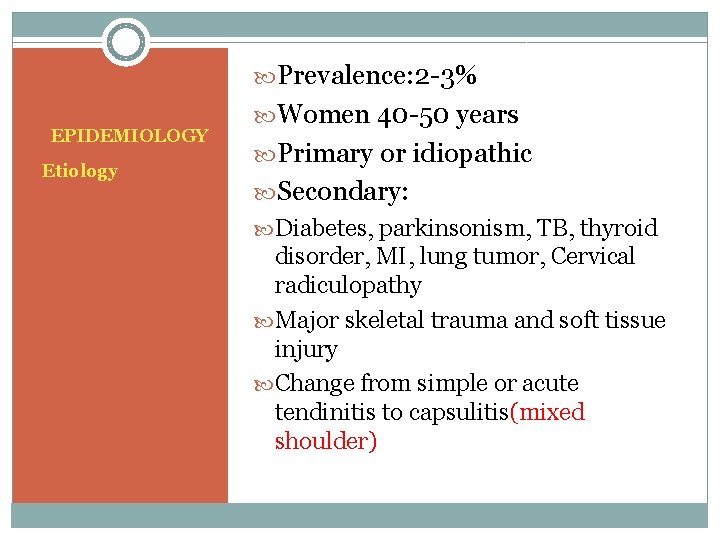

Prevalence: 2 -3% EPIDEMIOLOGY Etiology Women 40 -50 years Primary or idiopathic Secondary: Diabetes, parkinsonism, TB, thyroid disorder, MI, lung tumor, Cervical radiculopathy Major skeletal trauma and soft tissue injury Change from simple or acute tendinitis to capsulitis(mixed shoulder)